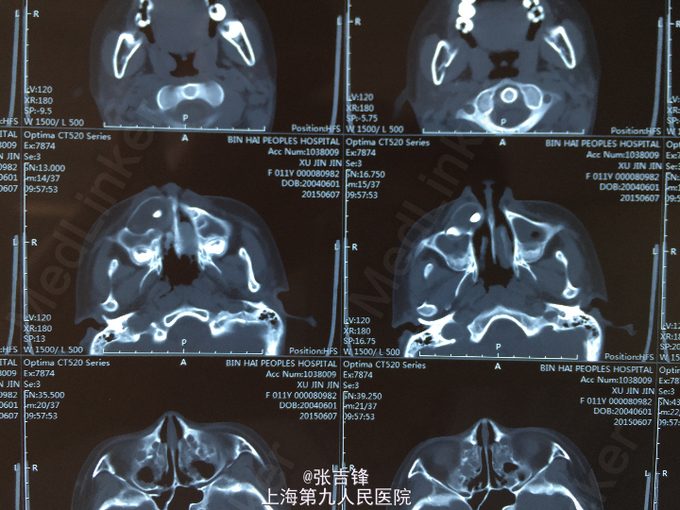

面部不对称,右上颌膨隆,口内混合牙列期,4I脱落,16、26、36、46已萌出,口内余为乳牙,右上颌前庭沟隆起,乒乓,穿刺得淡黄色囊液 全景片:右上颌骨囊肿,13-23 34-44,恒牙胚先天性缺如 CT:上颌骨含牙囊肿

上颌骨囊肿 恒牙胚部分缺如 治疗方案:先行上颌骨囊肿开窗减压术,待囊肿缩小后再行手术